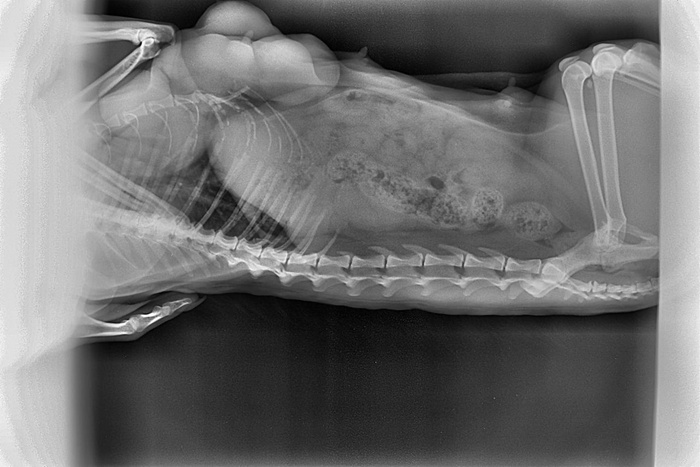

Дела не очень у неё. Под лопаткой и в одной из шишек обнаружили твёрдые уплотнения. Неясно какого качества. Ветеринар сказал надо делать рентген грудной клетки. Если доброкачественная опухоль, попробовать удалить. Если нет, то не стоит мучить кошку, тут сколько уж проживёт.

С Масей съездили на рентген по поводу уплотнений, ждём что скажет врач. Даём лактостоп 10 дней (пока взяли в долг 600₽-)